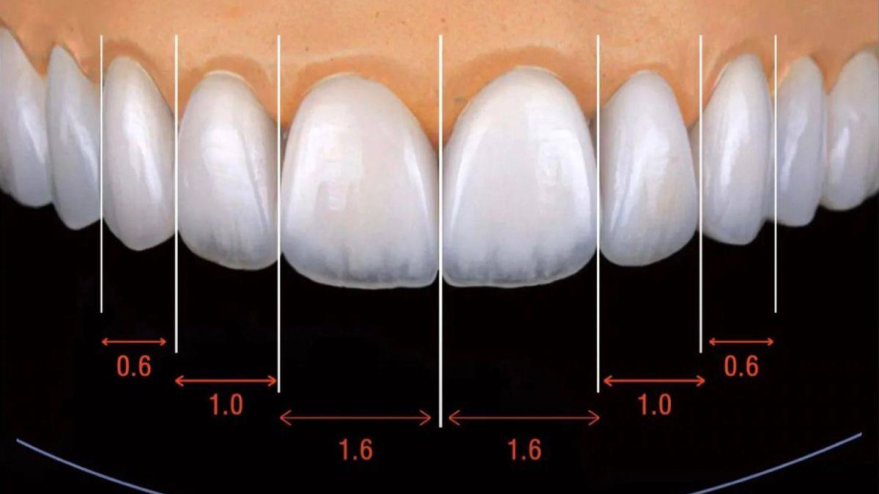

Керамические виниры Е-МАХ – лучший выбор для создания идеальной улыбки. Толщина всего в 0,3 мм и особые свойства керамики позволяют с точностью повторить натуральную эстетику вашей улыбки.

Прессованная керамика Е-МАХ, разработанная компанией Ivoclar – единственный на сегодня материал, из которого возможно создать накладку, в точности повторяющую естественный цвет и прозрачность зуба.

Е-МАХ в 2 раза тоньше виниров из обычной керамики или композита, при этом они крепче и устойчивы к ежедневным нагрузкам на зубы.